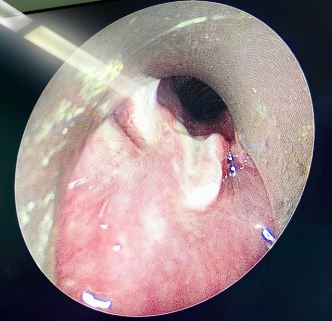

Y型支架术后球囊扩张塑形

2026年3月31日下午3时,在费卫东等麻醉团队密切配合下,先对患者进行全麻、肌松,呼吸介入专家俞小卫带领下,黄燕华、陈意、刘志光主任紧密配合,利用STOZE 成像系统引导,成功插入硬质气管镜鞘管,在高频通气保驾下,置入导丝,沿导丝插Y形支架到位后逐步释放支架,支架到位,最后采用球囊对支架进行扩张塑形,支架贴壁良好。